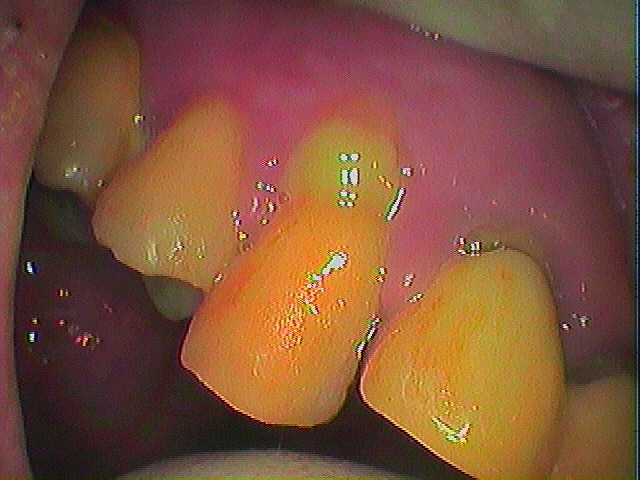

術前はこのように縁上歯石がかなりついています

歯も少し動揺が認められます